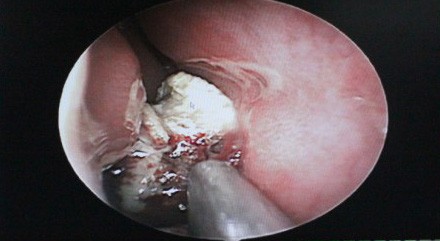

鼻内镜下发现徐小姐右鼻腔内有未知脓肿物存在

经过全面的检查并取得了小徐本人的同意后,医生决定为小徐实施手术。1月5日,手术开始。西安新城中大耳鼻喉医院耳鼻喉科副主任医师来长荣来长荣在局麻鼻内镜下为小徐进行了右鼻腔肿物切除术,手术中终于见到了那个未知的脓肿,竟然是一块直径约2cm的橡皮异物,由于时间太长,橡皮表面钙化结晶盐形成,堵塞在了下鼻道和鼻中隔之间。在鼻内镜下去除异物之后,来长荣又进行了右侧筛窦开放、蝶窦口扩大术,清理了蝶窦腔内囊肿,较后以明胶海绵填塞右侧鼻腔,手术顺利完成。